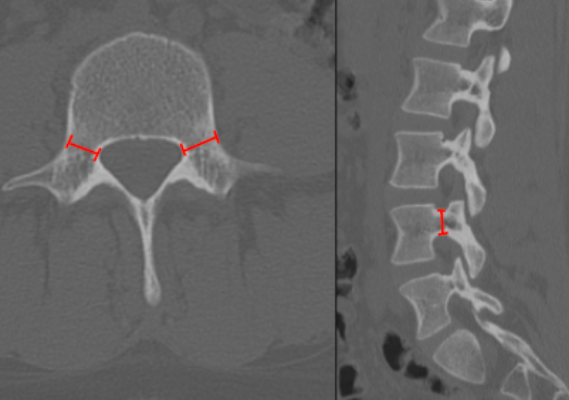

Interpedicular Distance

Pedicle Dimensions